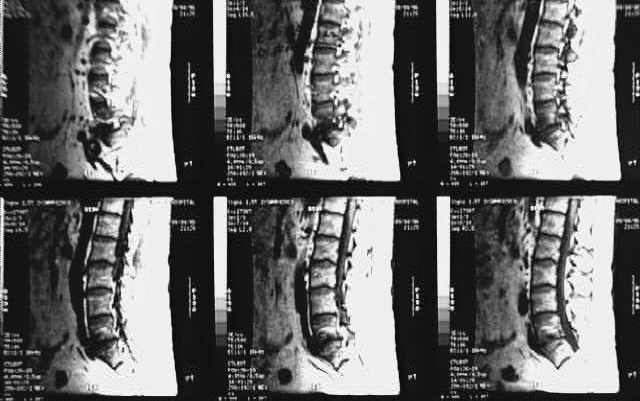

Radiology Images

Back- Lumbar Spine MRI Sagittal 3